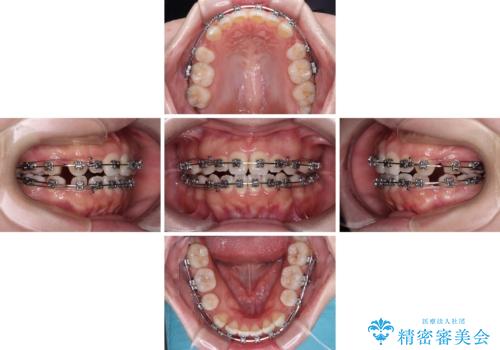

- メタルブラケット

- 1年9ヶ月

- 10-30回

当初は舌のトレーニングをしっかりと行ってくださったおかげで、短い期間で治療を終えることができました。